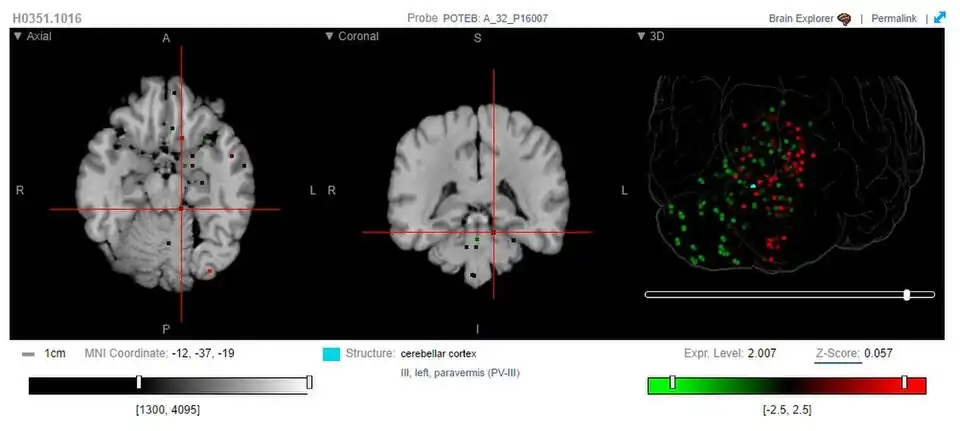

Some studies have used POTEB probes to study the expression of POTEB in the human brain. However, the only region with notable POTEB expression is the cerebellar cortex, responsible for motor function and some cognitive functions.[14]

This image shows the expression of POTEB in the human brain, around the cerebellar cortex region.